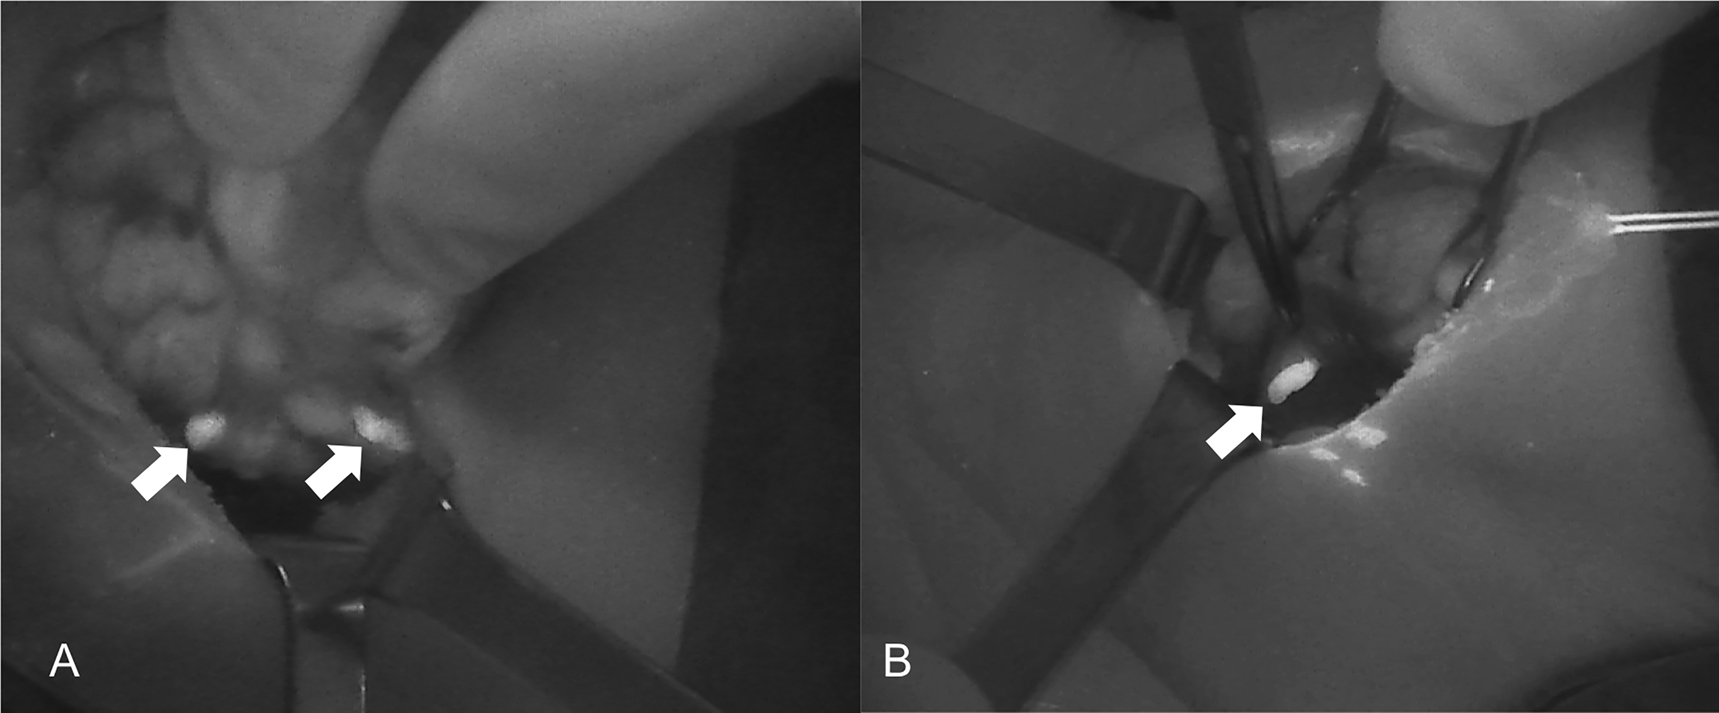

The introduction of NIRAF has vastly improved intraoperative imaging [47, 48]. Many recent studies (Table 2) have demonstrated that the use of NIRAF during thyroid surgery can improve surgical outcomes by facilitating PG identification (Figures 1 –3), which reduces the incidence of postoperative hypoparathyroidism. In particular, Benmilloud et al. showed that NIRAF improved PG identification and helped to reduce the rate of temporary postoperative hypocalcemia, parathyroid autotransplantation, and inadvertent parathyroid resection [48, 66]. In the literature, NIR devices have been shown to facilitate parathyroid gland identification by detecting their AF before conventional, visual recognition by the surgeon, in 37–67% of cases [49]. Additionally, these devices enable the early identification of PGs before surgical dissection, helping to preserve their vasculature [50]. A systematic review and meta-analysis by Barbieri et al. found that NIR fluorescence imaging reduced short and medium-term hypocalcemia compared to conventional surgery [51]. Moreover, NIRAF can detect subcapsular/intrathyroidal PGs or PGs that have been accidentally removed, which can then be resected from the thyroid specimen and auto planted back into the patient (Figures 4 and 5). In addition to the identification of normal PGs, NIRAF can help to identify a pathological PG. Parathyroid adenomas exhibit a more heterogeneous and less intense autofluorescence signature than that of normal PGs (Figure 6), enabling the differentiation between a normally functioning and a pathological PG [52, 53]. Furthermore, the fluorophore is resistant to freezing, heating, and fixing with formalin, meaning that the autofluorescence properties are preserved after gland resection [4, 29, 42, 43].

A sequence of near-infrared autofluorescence (NIRAF) images showing a parathyroid gland (PG), indicated with a white arrow. (A) Autofluorescence of the PG prior to injection of indocyanine green (ICG). (B) and (C) Diffusion of the ICG contrast agent, showing a well-vascularized PG.